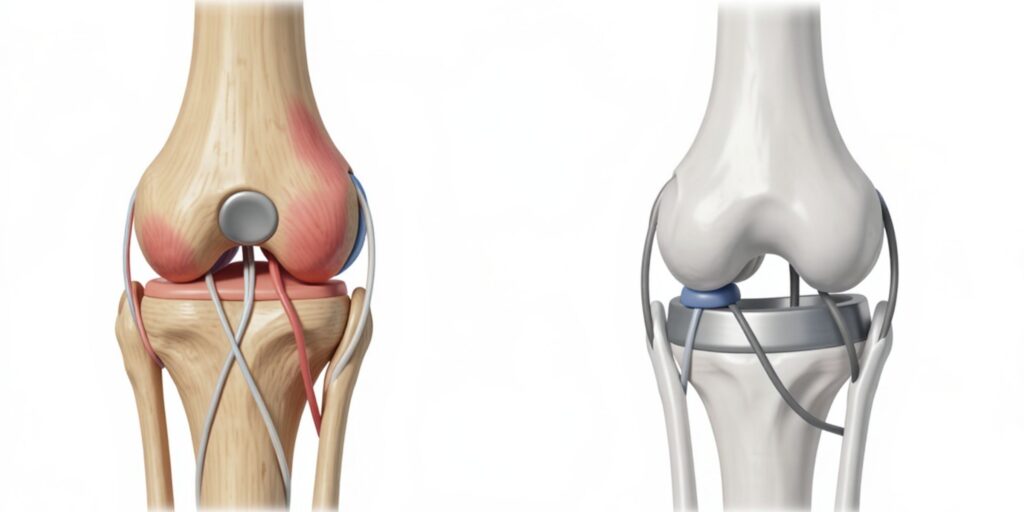

Whenever feasible, joint preservation techniques are prioritised over complete joint replacement. By retaining healthy cartilage, ligaments, and supporting structures, natural movement patterns can often be maintained. Preserving the native joint may support better long-term function in selected cases.

Each tumour location and extent requires an individualised approach. Reconstruction may involve bone grafting, specialised implants, or biological techniques depending on the case. Careful post-operative rehabilitation planning ensures gradual return to daily activities with improved confidence and function.